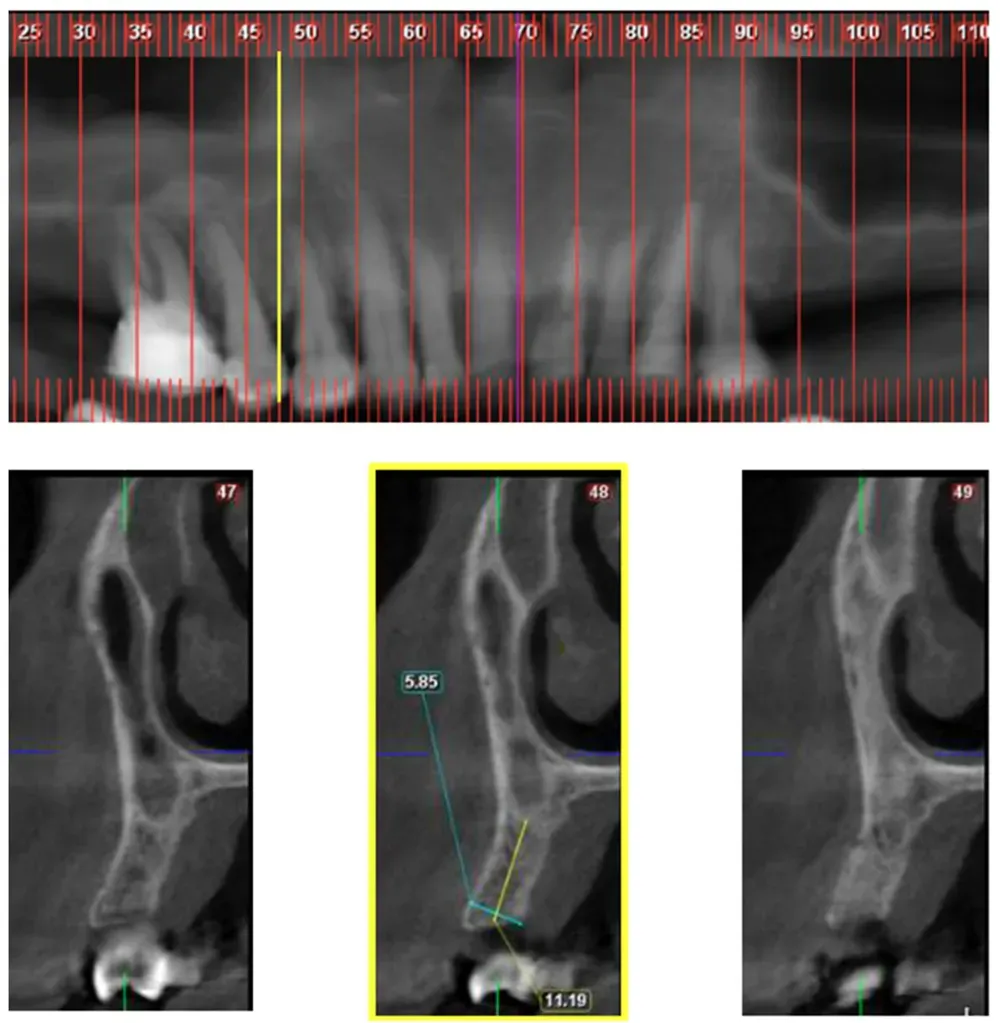

Personalmente, l’ho notato abbastanza frequentemente. Mi capita anche di vedere in giro radiografie dove il mini-rialzo “del seno” è in realtà “del naso”. Va benissimo lo stesso.

Yahya e collaboratori hanno sviluppato un sistema di classificazione che divide questa variante in classi orizzontali mesio-distali e divisioni verticali. Ma ciò che sorprende di più in questo interessante articolo è la frequenza relativamente alta della variante riscontrata dagli autori. (https://doi.org/10.3390/jcm10194293)

Nella Classe 1, il confine tra la cavità nasale e l’antro mascellare si trova sopra la parte distale del canino. In base ai dati raccolti in questo studio, si trova nel 17.2% dei casi.

La Classe 2, dove il confine naso-sinusale si trova tra il margine distale del canino e quello del secondo premolare, appare nel 66% dei casi esaminati. La Classe 3, con il confine distale al margine mesiale del primo molare, si manifesta nel 16,8% dei pazienti.

La distribuzione verticale rivela pattern ancora più interessanti, classificati dagli autori in divisioni. Vedi figura sotto.

Da sinistra a destra—Sezioni trasversali CBCT: Divisione A (Div. A): Cavità nasale da sola; Divisione B (Div. B): Cavità nasale adiacente alla cavità sinusale; Divisione C (Div. C): Cavità sinusale da sola sopra la cresta alveolare; Divisione D (Div. D): La cavità nasale è posizionata in posizione superiore rispetto alla cavità sinusale. Da Yahya et al. (2021). Licenza CC4.0.